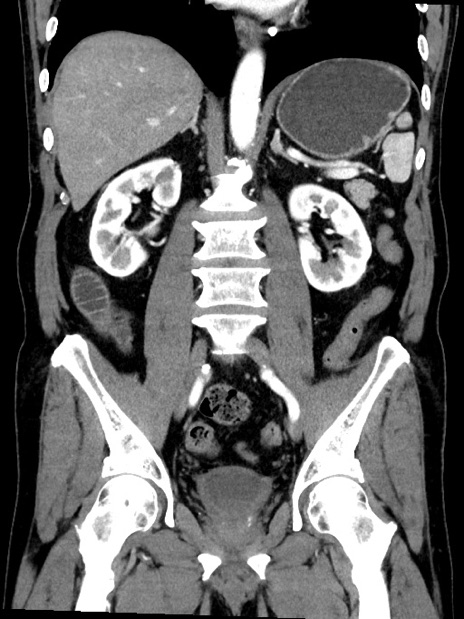

症例35(冠状断像)

【症例】70歳代 男性

【主訴】腹部膨満、嘔吐

【現病歴】昨日より腹部膨満感出現。本日増悪し、仙痛出現。嘔吐あり、受診。

【既往歴】糖尿病、胆摘後

【身体所見】BP 149/80mmHg、HR 74/min、BT 35.9℃、腹部:膨満、軟、圧痛なし。腸雑音減弱あり。上腹部正中切開瘢痕あり。

【データ】WBC 13500、CRP 1.72